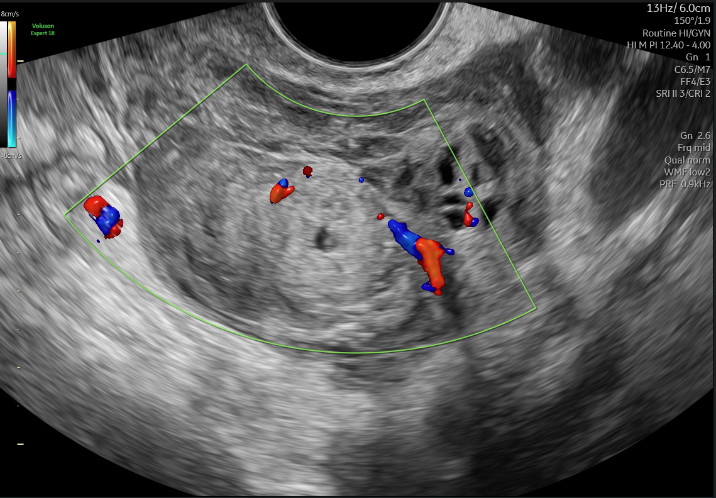

Hình 1. Hình ảnh siêu âm tử cung phần phụ

Chẩn đoán: Thai ngoài tử cung trái đã vỡ (một tình huống có thể gây xuất huyết nặng và nguy hiểm tính mạng nếu không được xử trí kịp thời).